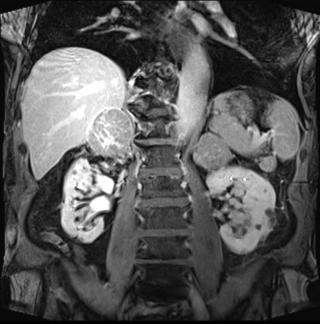

(Слева) На рисунке показано сосудистое образование почки с видимыми жировым и мягкотканным компонентами. Обратите внимание на крупные «питающие» артерии. Такая гиперваскуляризация предрасполагает эти опухоли к спонтанным кровотечениям.

(Справа) УЗИ в сагиттальной плоскости: эхогенное образование в коре верхнего полюса левой почки вследствие случайно обнаруженной ангиомиолипоме (АМЛ). Цветовой поток в данном образовании отсутствует. (Слева) КТ без контрастирования, аксиальная проекция: у этого же пациента выявлено образование жировой плотности В в коре верхнего полюса левой почки. Данные признаки характерны для ангиомиолипомы (АМЛ).

(Справа) МРТ, постконтрастное Т1, режим подавления сигнала от жировой ткани, аксиальная проекция: обнаружена ангиомиолипома (АМЛ), которая распространяется в околопочечное пространство. Дефект коры (признак «желобка»), указывающий на происхождение ангиомиолипомы (АМЛ) из ткани почки. Крупный сосуд продолжается в новообразование из почки.